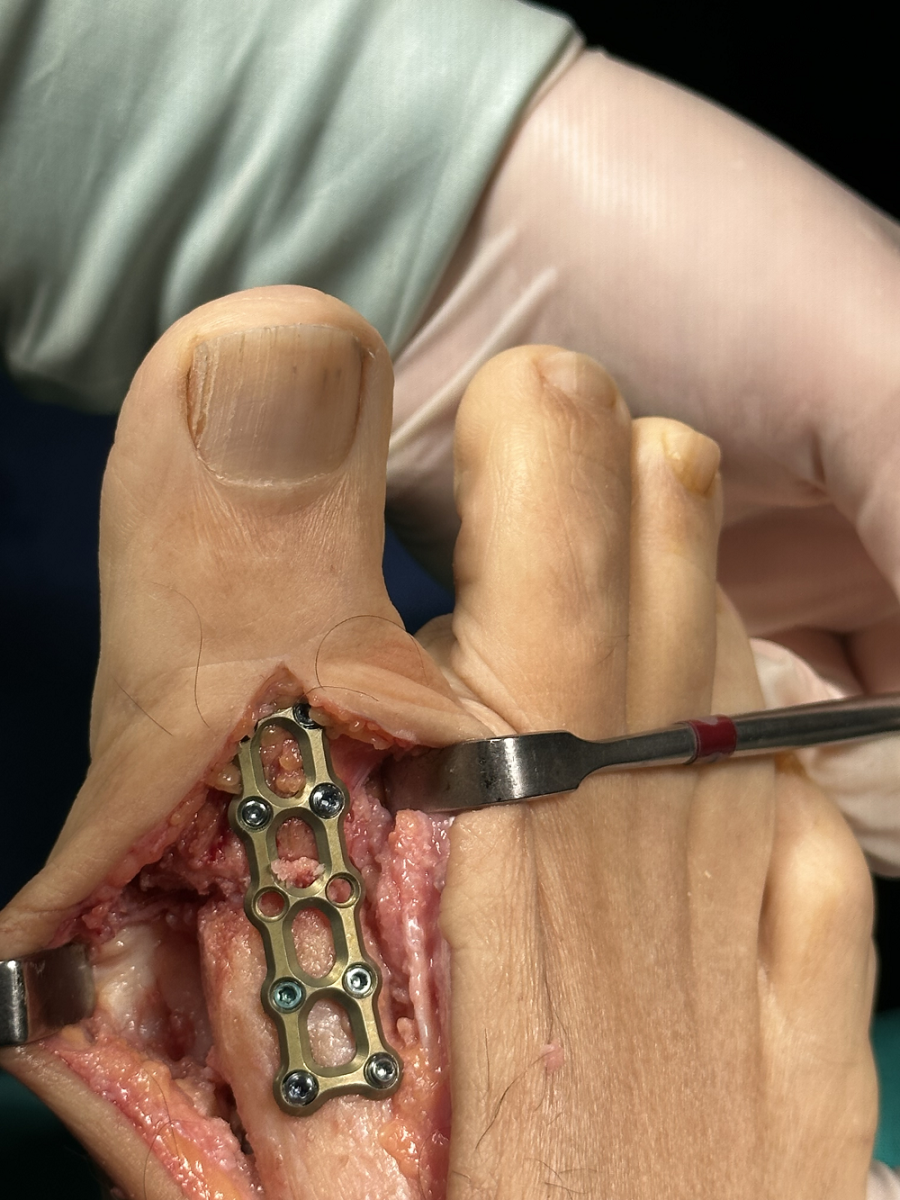

Artrodez: Ayak başparmağının kıkırdak hasarı ciddi olduğunda genellikle kemiklerin birbirine kaynaştırılması (artrodez) önerilir. Artrodez sırasında eklemin kalıcı bir pozisyonda sabitlenmesi için, vidalar veya plak kullanacaktır. Şiddetli halluks rijiduslu veya çeilektominin başarısız olduğu hastalarda ağrıyı azaltmanın en güvenilir yolu artrodezdir.